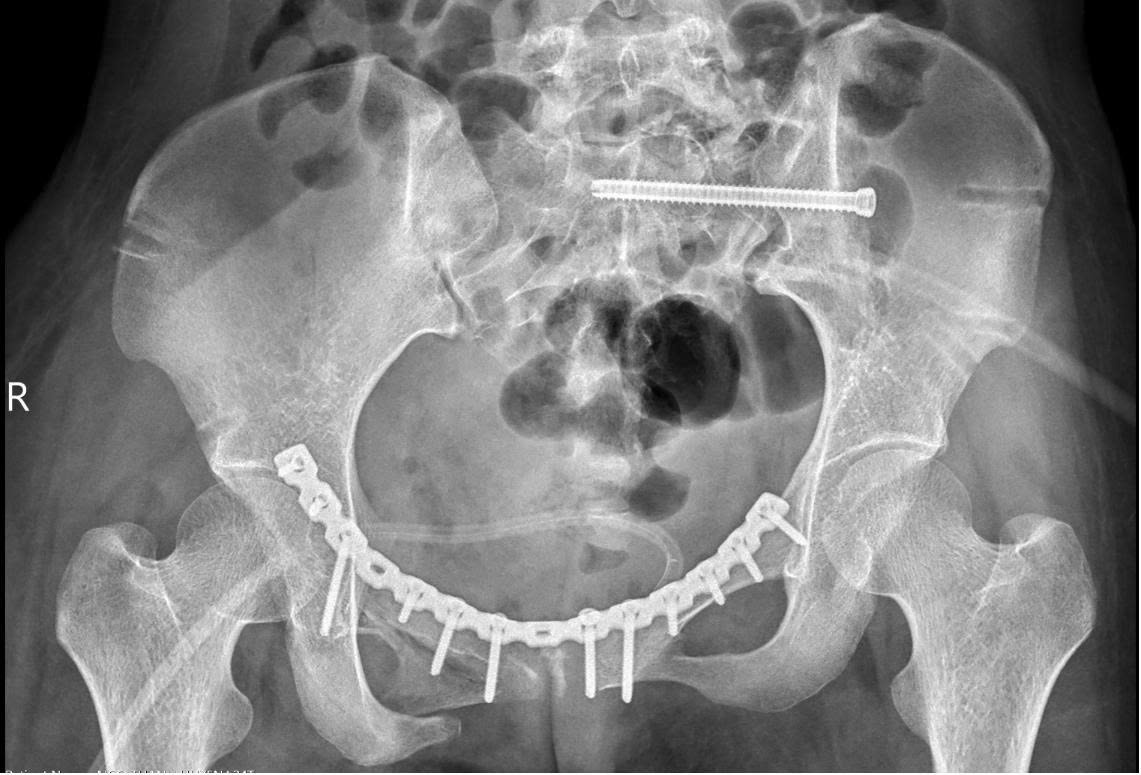

Hình ảnh X-quang sau phẫu thuật cho thấy khung chậu bệnh nhân đã được cố định vững bằng hệ thống nẹp vít và vít chậu cùng. Cấu trúc vòng chậu được tái tạo, giúp bệnh nhân có thể tập vận động trở lại sau mổ.